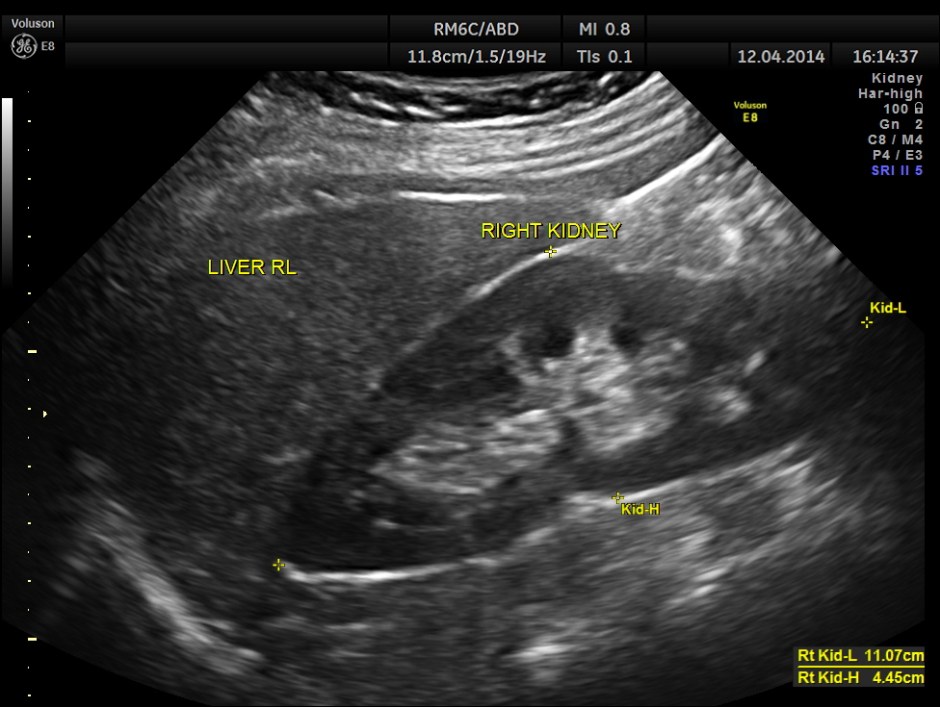

Both the kidneys appeared to be normal . No calculus was seen . There was no evidence of any obstruction.